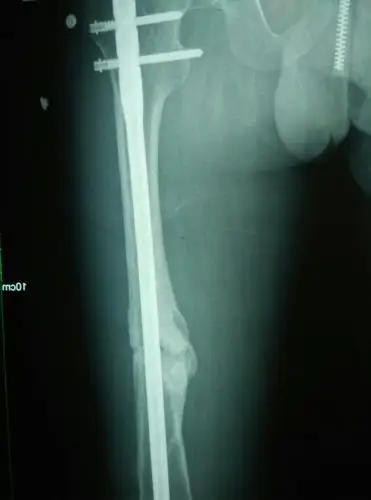

长骨痂了可以下地啦

术后三个月,x光片可见骨痂形成,患者恢复良好!家属满意!继续观察!

骨骨干骨折术后3个月骨折线模糊骨痂少.

伤后34天的x线片,骨折端有大量骨痂形成.